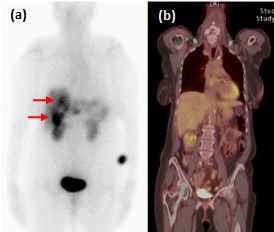

FDG-PET-CT é um exame de baixa sensibilidade na detecção de TNEs bem diferenciados (figura 2), ao passo que a taxa de detecção é alta em pacientes com Ki-67 superior a 15%. Em um estudo prospectivo, a sobrevida mediana de pacientes com FDG-PET-CT negativo e positivo foi de 119,5 meses e 15 meses, respectivamente (P<0,001) (BAHRI, 2014). Um FDG-PET-CT positivo, assim, sugere a necessidade de intervenções terapêuticas mais rigorosas.

Figura 2. Exames funcionais de tumor neuroendócrino bem diferenciado metastático. Captação em fígado (setas) ao Octreoscan (a), mas não ao FDG-PET-CT (b). Adaptado de Leung et al, 2013.